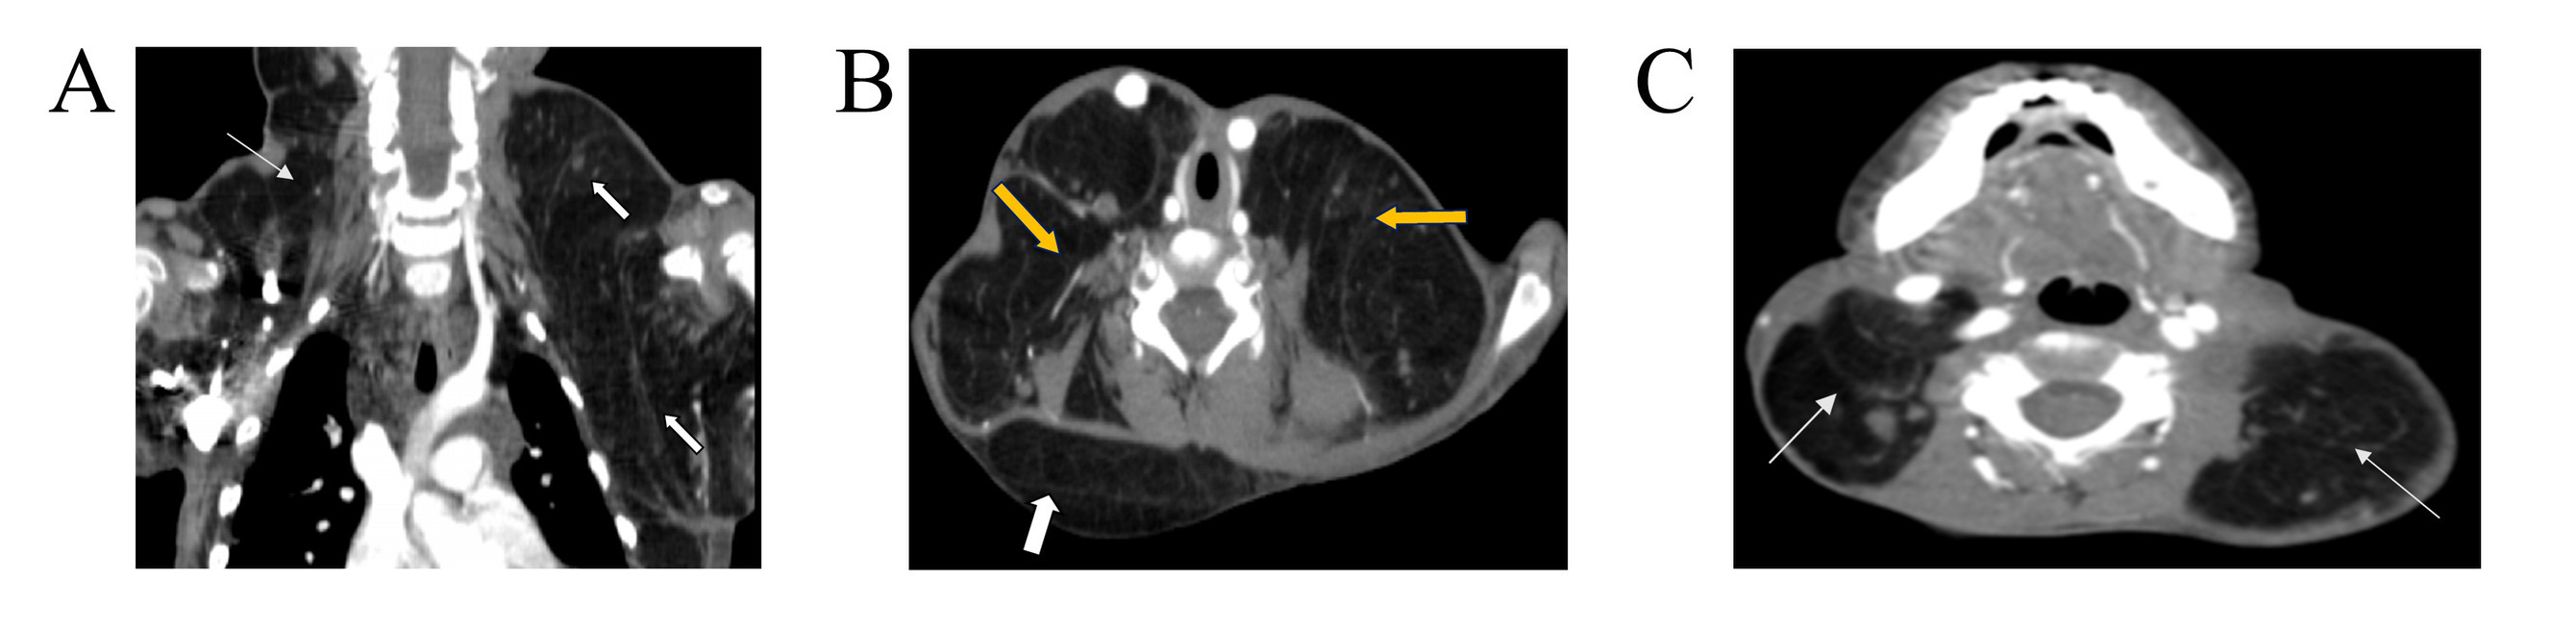

Carcinoma ex Pleomorphic Adenoma: A Case Series and Literature Review

Carcinoma ex pleomorphic adenoma (CXPA) is a rare malignant salivary gland tumor that can lead to severe complications and carries a risk of distant metastasis. This study aims to provide a comprehensive overview of CXPA through a case series and a review of the literature.

Six patients were included, with ages ranging from 45 to 88 years (mean ± SD: 64 ± 15.36; median: 62). Most were male (66.7%), with an even distribution of occupations. All presented with preauricular swelling lasting 2 to 10 years, and three had left-sided tumors. Fine needle aspiration identified 33.3% as benign and 16.7% as malignant. Ultrasound examination showed solid tumors in four cases, three of which were well-defined. Three (50%) underwent total parotidectomy, and three (50%) underwent superficial parotidectomy. Histopathological examination revealed adenocarcinoma ex pleomorphic adenoma in 50% and squamous cell carcinoma ex pleomorphic adenoma in 16.7%. Tumor sizes ranged from 3.5 to 6 cm (mean: 4.73 ± 1.24 cm). Capsular invasion was present in all cases, with lymph node involvement in 33.3%, lympho-vascular invasion in 16.7%, and perineural invasion in 50%. Adjuvant therapy included radiotherapy or chemoradiotherapy.